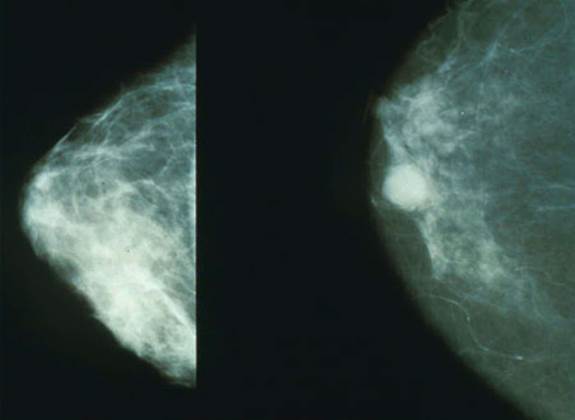

A Google artificial intelligence system proved as good as expert radiologists at detecting which women had breast cancer based on screening mammograms and showed promise at reducing errors, researchers in the United States and Britain reported. The study, published in the journal Nature on ...